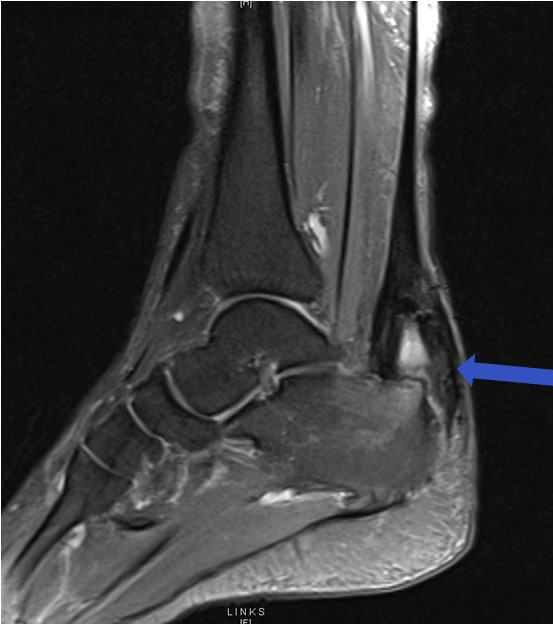

Ergänzend zur klinischen Diagnose kann zur Diagnosesicherung eine Sonographie oder MRT-Untersuchung der Achillessehne erfolgen. In der Sonografie lässt sich eine Verdickung und ggf. pathologische Gefäßeinsprossung im Sehnengewebe darstellen. Das MRT kann in verschiedenen Sequenzen Veränderungen innerhalb der Sehne nachweisen.